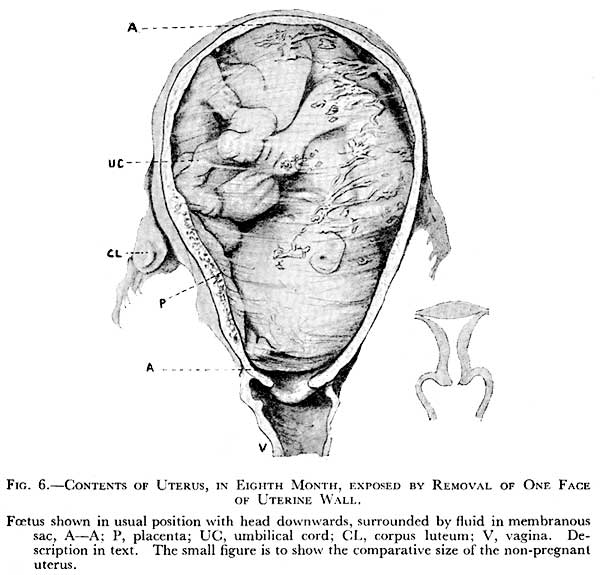

Prenatal Development | Introduction to Psychology

Pregnancy

Pregnancy

Human fetus – week 37 stock illustration. Illustration of uterus – 58830075

Fetal Development – Embryology

Weekly development of a human fetus – week 37.

Fetal Development: Week 28